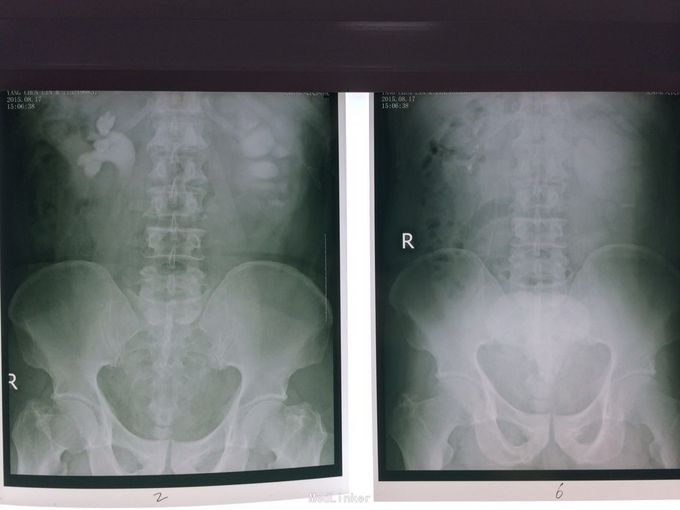

体检发现左肾积水3月余。无尿频尿急,排尿困难。当地医院彩超示:1双肾积水2右输尿管扩张3左侧输尿管走形迂曲并扩张4膀胱位置抬高5前列腺显示不清。为求进一步治疗前来我院。门诊行检查后诊断为盆腔脂肪增多症,建议患者行左肾造瘘。患者表示拒绝,至北京某医院就诊,给予行双侧输尿管D-j管置入,未成功。再次至我院就诊,门诊以“盆腔脂肪增多症”收住院。

盆腔脂肪增多症。彩超示右肾轻度积水。与患者沟通后局麻下行左肾穿刺造瘘。